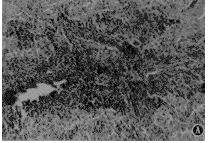

5.牛嗜铬细胞移植的形态学观察:经HE染色可见在PD鼠脑内移植部位呈圆柱形分布,有大量存活的非鼠脑组织细胞结构的外来细胞,细胞体积及胞核较大,此区可见有血管长入(图1)。

图1 牛肾上腺髓质嗜铬细胞移植入PD鼠脑纹

状体内6个月的HE染色 A×33;B×132